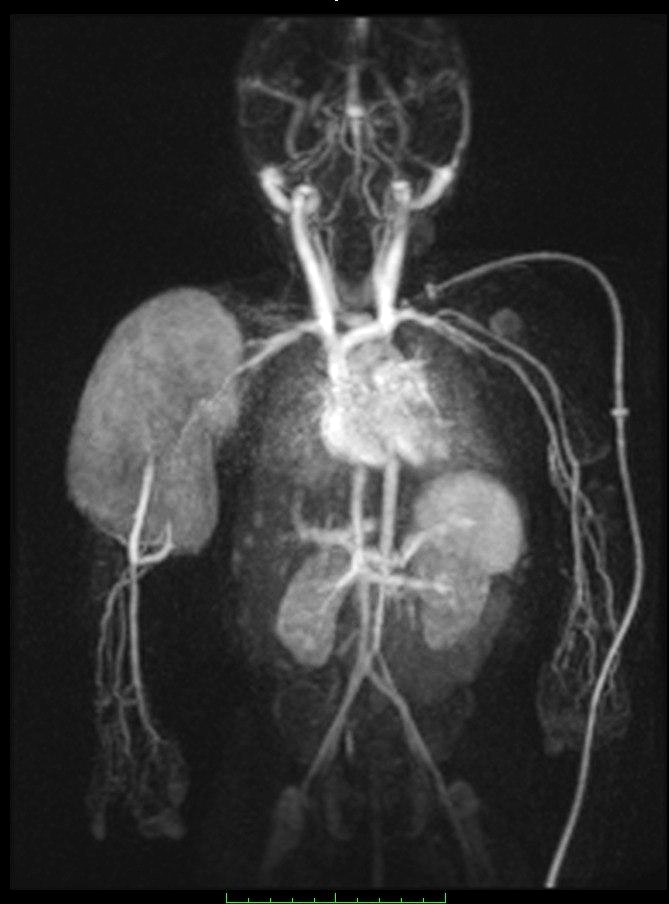

- МРТ: Створює найчіткіші зображення м’яких тканин, органів та судин. Без використання шкідливого випромінювання, тому також підходить для візуалізації вагітних, дослідженні плоду.

Завдяки передовим технологіям ми маємо можливість проводити МРТ дослідження “всього тіла” (whole body)*, мультипараметричні обстеження головного мозку та простати з наявними програмами МР-трактографії (DTI), МР-спектроскопії, також виконуємо безконтрастну МР-ангіографію інтракраніальних судин, шиї; МР-холангіопанкреатографію, ентерографію, визначення перенавантаження залізом печінки.

Магнітно-резонансна томографія: Найточніший метод для дослідження мозку, хребта, суглобів та м’яких тканин. Абсолютно безпечний тому також підходить для візуалізації вагітних, дослідженні плоду. Разом КТ та МРТ показані для виявлення вроджених аномалій розвитку/патології центральної нервової, скелетно-м’язової, травної, дихальної, сечовидільної системи, статевої сфери Також показані пацієнтам та потенційним донорам при підготовці до трансплантації,